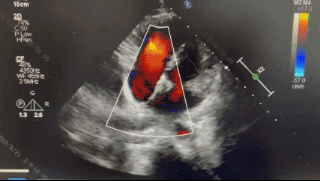

术后6个月随访

超声报告:(1)房间隔封堵器位置正常,伞盘可见部分降解,各瓣叶形态活动未见异常,右心比例稍大,左房室腔不大,心包腔内未见液性暗区; (2)多普勒检查:房水平未见残余分流;心功能:室壁运动协调,未见节段性异常;(3)先天性心脏病房间隔缺损封堵术后(可降解)未见残余分流。

传统的金属封堵器因其不可降解性,植入后会终身留存于患者体内,可能引发组织压迫、磨蚀、血栓等长期并发症风险。然而生物可降解房间隔缺损封堵器由生物高分子材料构成,植入后一年左右即可降解为水和二氧化碳,既避免了金属异物的长期影响,又能促进心脏的自然修复。因此术者经综合考虑后,选择了BDASD-I 14封堵器,并在纯超声引导下完成手术,不仅减少了患者和医生的辐射暴露,也进一步提高了手术的精准度和安全性。术中封堵器精准展开并锁定,术后即刻超声检查未见残余分流;术后1周心超复查均可见封堵器形态位置良好,稳定夹持缺损;术后3个月随访超声下可见封堵器位置结构正常,无残余分流;术后6个月随访可见封堵器位置正常,伞盘可见部分降解,无残余分流,封堵效果良好。